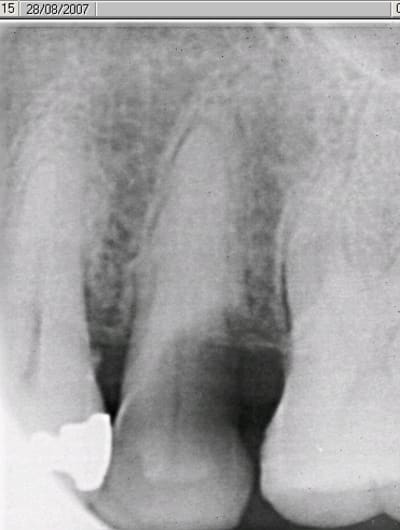

mais dans la mesure du possible implantes tout de suite. Ci joint radio d'une prémolaire que je vais extraire demain matin avec implantation immédiate.

suite de la prémolaire fracturée: extraction , mise en place d'un implant tekka diametre 4 longueur 15 mm pour aller chercher un bon ancrage primaire. Il y avait 2 mm d'espaceentre l'implant et la corticale en vestibulaire et 1 mm en palatin, j'ai comblé au bio-oss et tracté la muqueuse sans tensions pour le recouvrir.